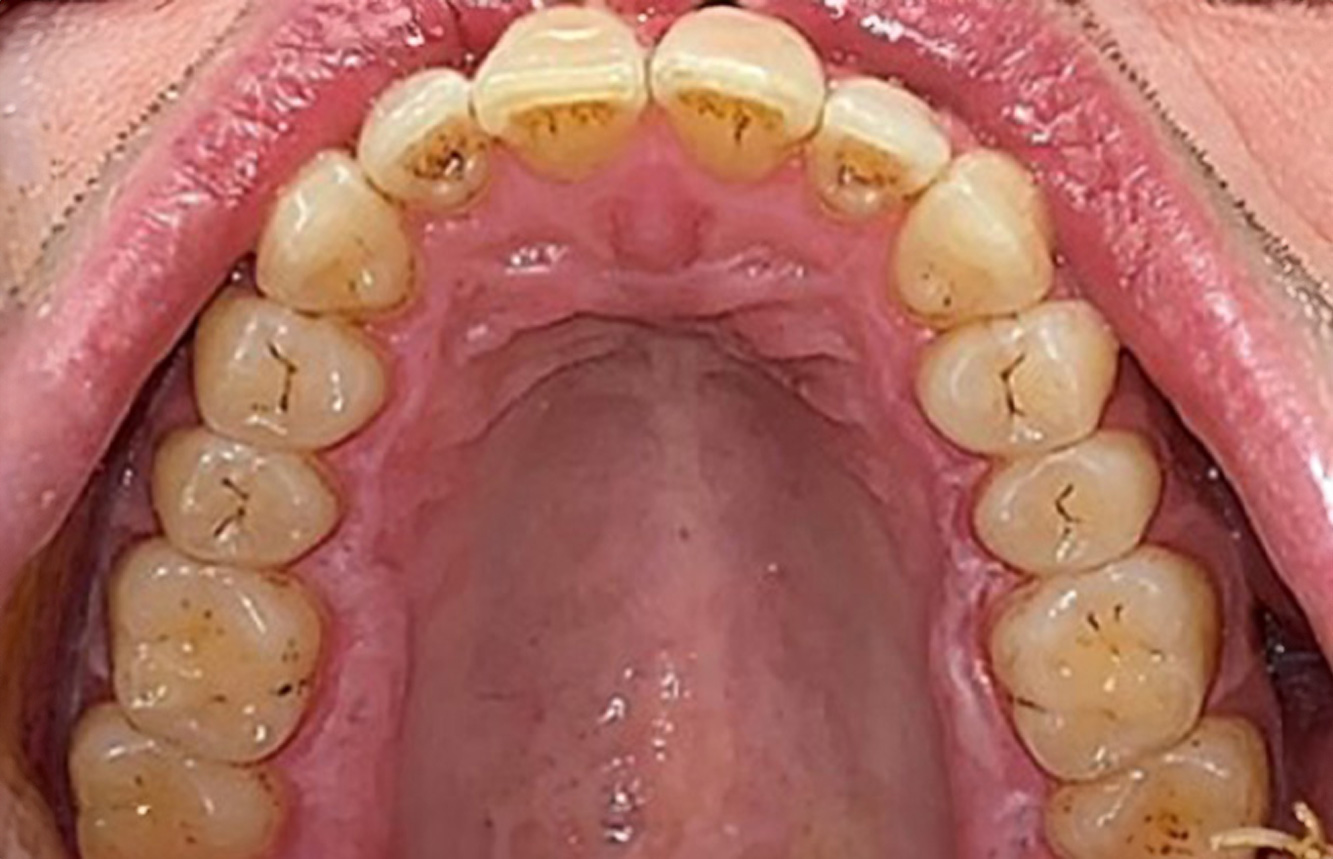

Der Transplantationspatient mit Gingivawucherungen

Ein 71-jähriger Patient mit Z.n. Nierentransplantation und Hypertonie (Bluthochdruck) stellt sich vor. Bedingt durch die Krankengeschichte ist eine Dauermedikation mit Cyclosporin, zur Unterdrückung der Immunabwehr, und Amlodipin, zur Blutdrucksenkung, erforderlich. Außerdem berichtet der Patient über empfindliches Zahnfleisch und Zahnfleischbluten. Aus mundgesundheitlicher Sicht zeigt sich ein saniertes Gebiss mit acht fehlenden Zähnen, ausgeprägte Gingivawucherungen, eine Parodontitis Stadium II, Grad B mit aktiven Taschen und eine initiale Wurzelkaries an Zahn 22. In der Kariesrisikoabschätzung wird ein mittleres Kariesrisiko (API 60) festgestellt. Für die Prophylaxesitzung lassen sich folgende Behandlungsempfehlungen ableiten. mehr Infos